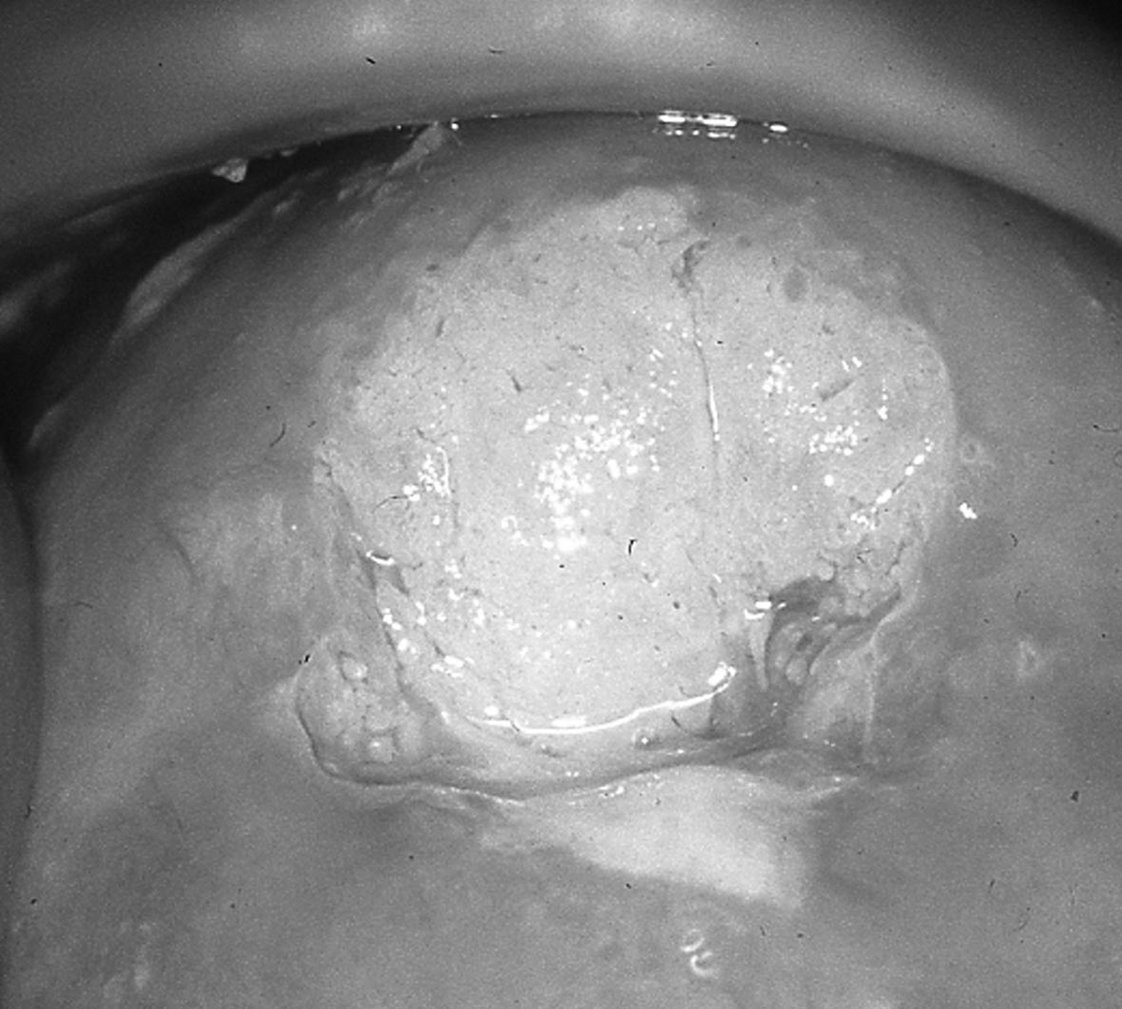

Le test de Schiller : l’application de lugol provoque une coloration brune homogène, transitoire (environ 10 minutes) et d’intensité proportionnelle à la teneur en glycogène des couches superficielles de la muqueuse. Les muqueuses malpighiennes atrophiques, immatures ou dysplasiques, la muqueuse glandulaire et les zones ulcérées sans revêtement malpighien ne se colorent pas (aspect jaune) (figure 18.9).

Figure 18.9 Zone lugol négative au test de Schiller correspondant à une CIN 3 à la biopsie

Figure 18.9 Zone lugol négative au test de Schiller correspondant à une CIN 3 à la biopsie.